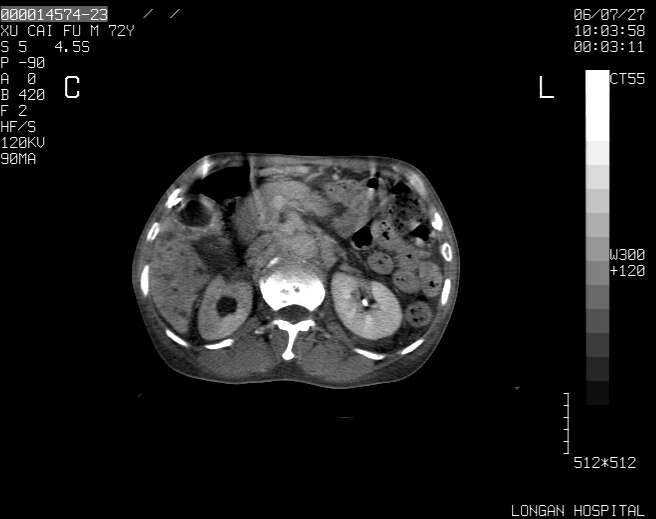

以下是引用winter在2006-7-30 20:14:00的发言:[br]1、考虑胆囊癌伴胆道侵犯并高位胆道梗阻、肝内多发转移、腹膜后淋巴结转移。[br]2、右肾轻度积水。[br]3、老人家72岁了胰腺头体尾部均较饱满,不过未见密度异常及其他异常征象。[br]4、腹水。

以下是引用jiajie在2006-7-31 7:10:00的发言:[br]考虑肝转移瘤,腹膜后淋巴结增大。[br]胃癌不能除外,建议胃镜检查。